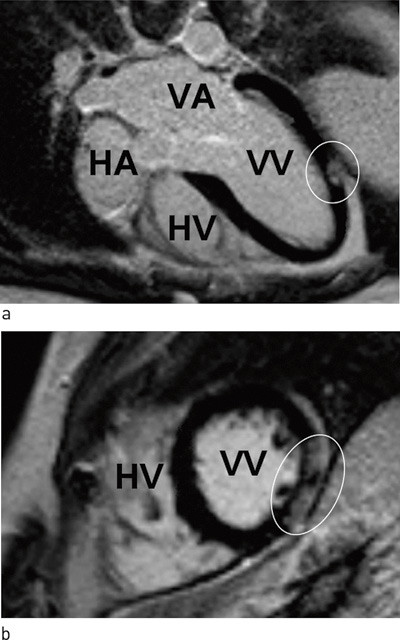

Kontrastbasert MR vil kunne avdekke uoppdaget gjennomgått myokardinfarkt, slik som vi fant hos en av pasientene som hadde angiografisk normale koronararterier. Ved myokardinfarkt på grunn av en okkludert koronararterie vil alltid kontrastoppladningen følge distribusjonsområdet til koronararterien og være subendokardial med varierende grad av transmuralitet (fig 2). Ved myokarditt vil kontrastoppladningen være epikardial og ikke følge koronararteriens forsyningsområde (fig 3). Det kan oppstå vansker med diagnostisering av myokardskade på grunn av myokarditt i forhold til myokardskade på grunn av myokardinfarkt dersom det samme området av myokard er rammet.